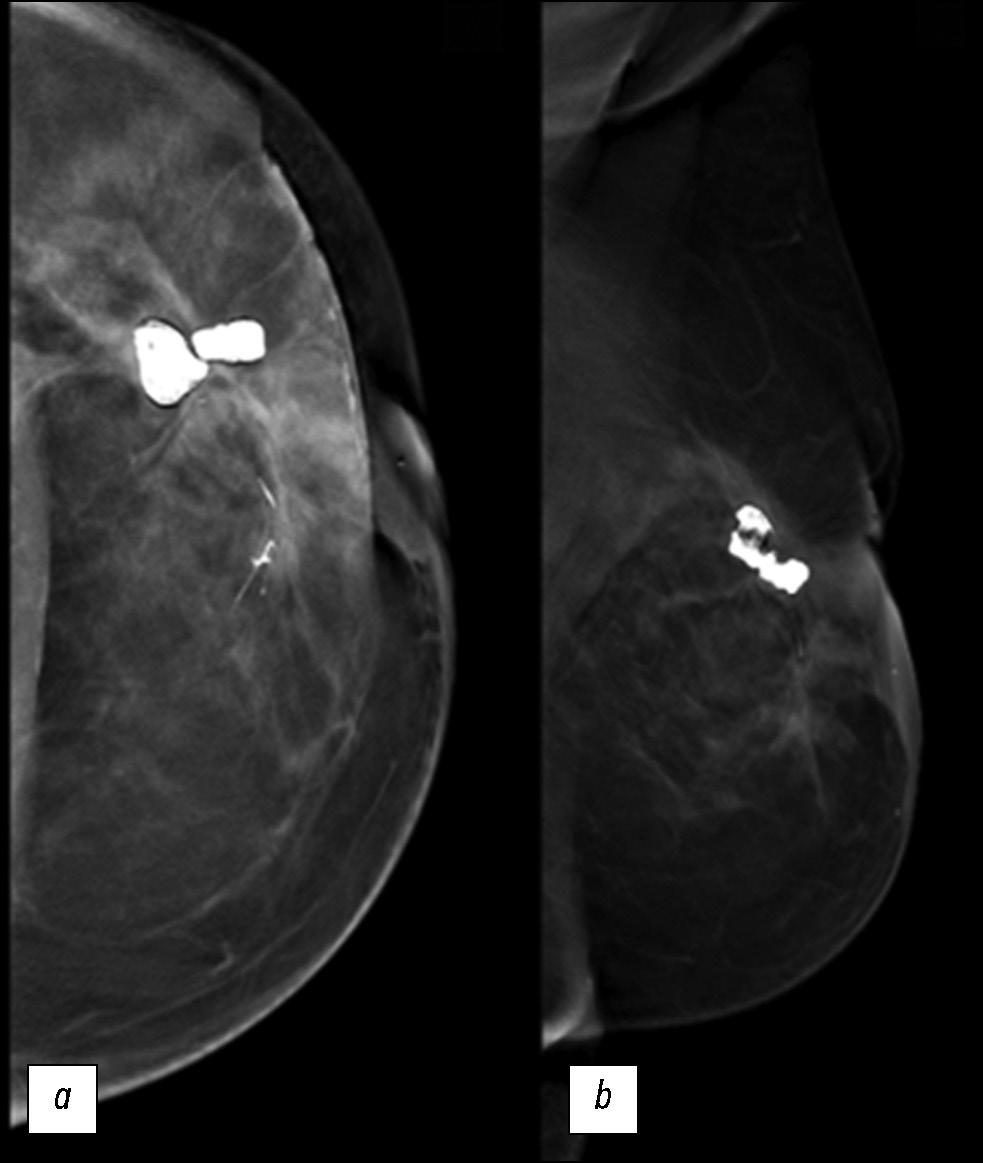

При проведении маммографии визуализировалось гетерогенное образование с неровными нечёткими краями и сопутствующими структурными деформациями, которое распространялось преимущественно в верхний наружный квадрант левой молочной железы и проходило вблизи крупных липонекротических кальцинатов. Наблюдалось также выраженное утолщение кожных покровов. Диаметр очага составил приблизительно 7 см (рис. 1).

Рис. 1. Маммограммы: а — краниокаудальная проекция; b — медиолатеральная (косая) проекция. В верхнем наружном квадранте левой молочной железы наблюдается рентгеноконтрастный очаг, связанный с деформацией паренхимы в результате квадрантэктомии.